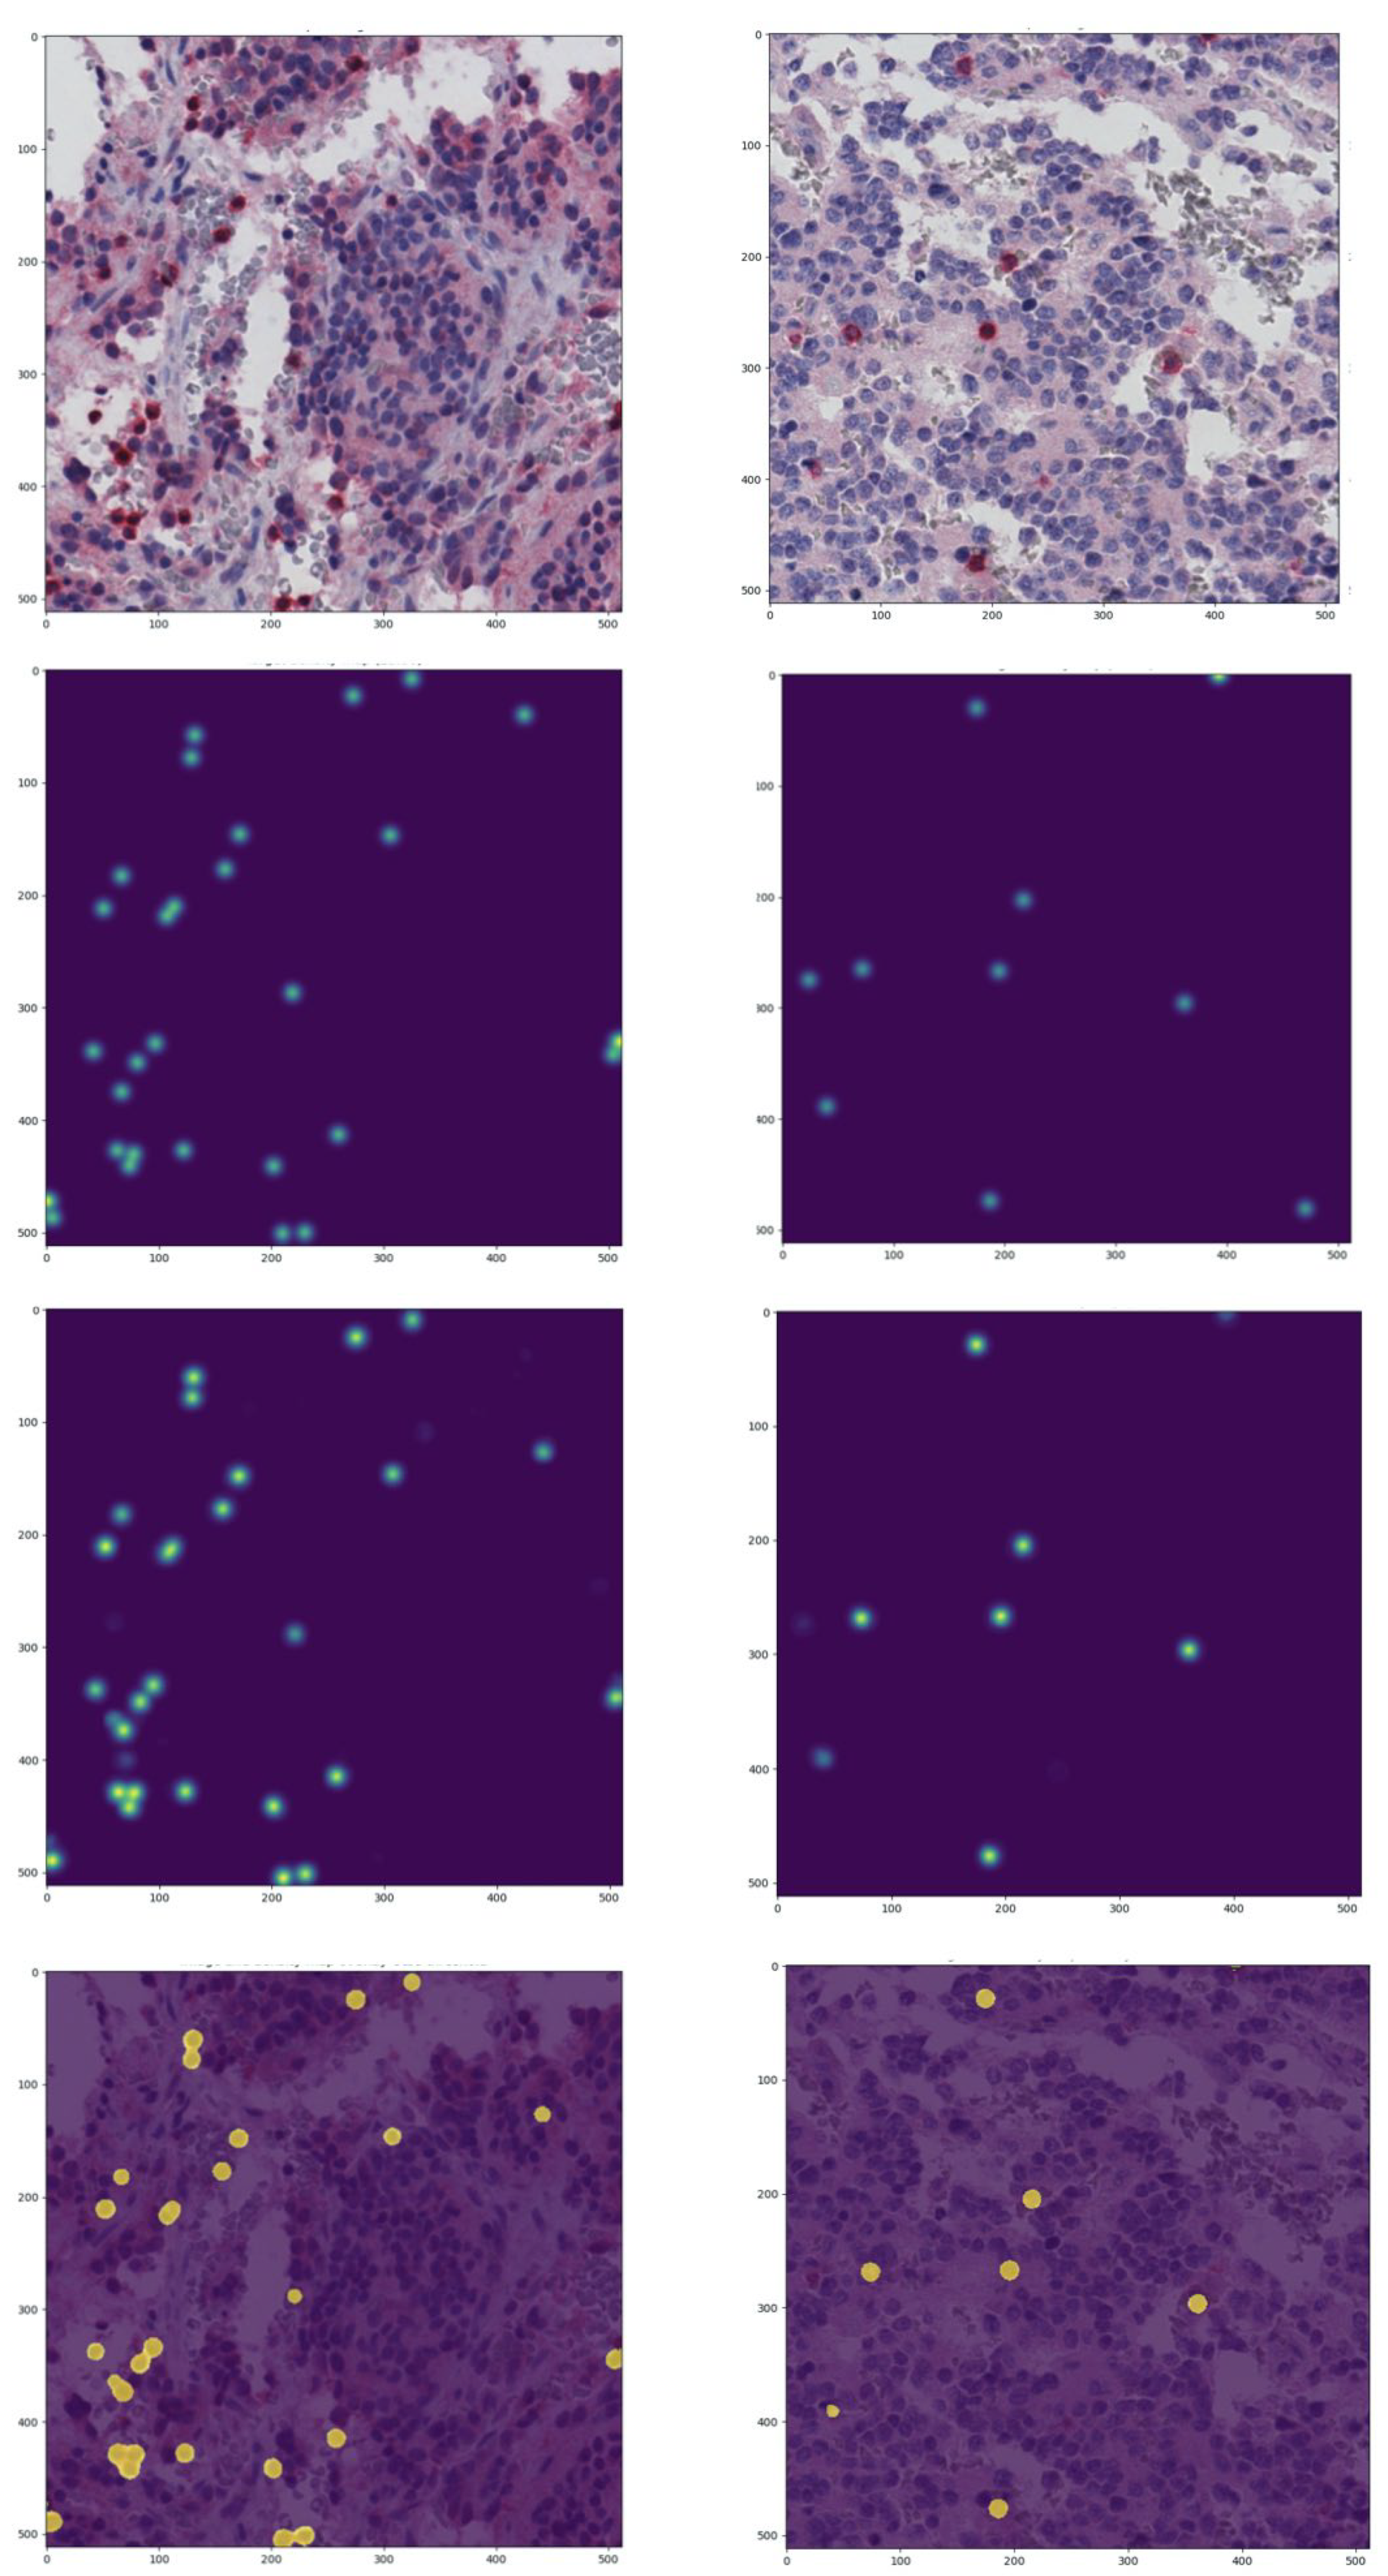

3.1. Quantification of the Immune Content

- First, the predicted density map values are corrected by setting to zero all pixels with negative values. Indeed, the model learns to predict near-zero values for pixels not belonging to lymphocytes, but the prediction may tend to zero in both positive and negative direction, and for the prediction to be a valid density map the negative values should be removed.

- Secondly, Otsu thresholding algorithm [132] is used to find an optimal value to discretize the density maps in two levels: lymphocytes and background. The Otsu algorithm is the de facto standard for discriminating foreground and background pixels within an image. In detail, the optimal threshold is identified by minimizing intra-class intensity variance (equivalent to maximizing inter-class variance). Since the Otsu algorithm is the one-dimensional discrete analog of Fisher’s discriminant analysis, this procedure coincides with globally optimizing k-means clustering on the intensity histogram. Pixels with values under the threshold are assigned to the background, while pixels with values over the threshold are assigned to the lymphocyte class.

- Thirdly, in crowded scenarios, the simple segmentation may still result in connected components including more than one pixel. To split connected components on the Otsu mask, the Watershed segmentation algorithm [133] is used to effectively separate a dense single connected component into multiple sub-components. The result of the Watershed technique is a matrix with n connected components with different labels.